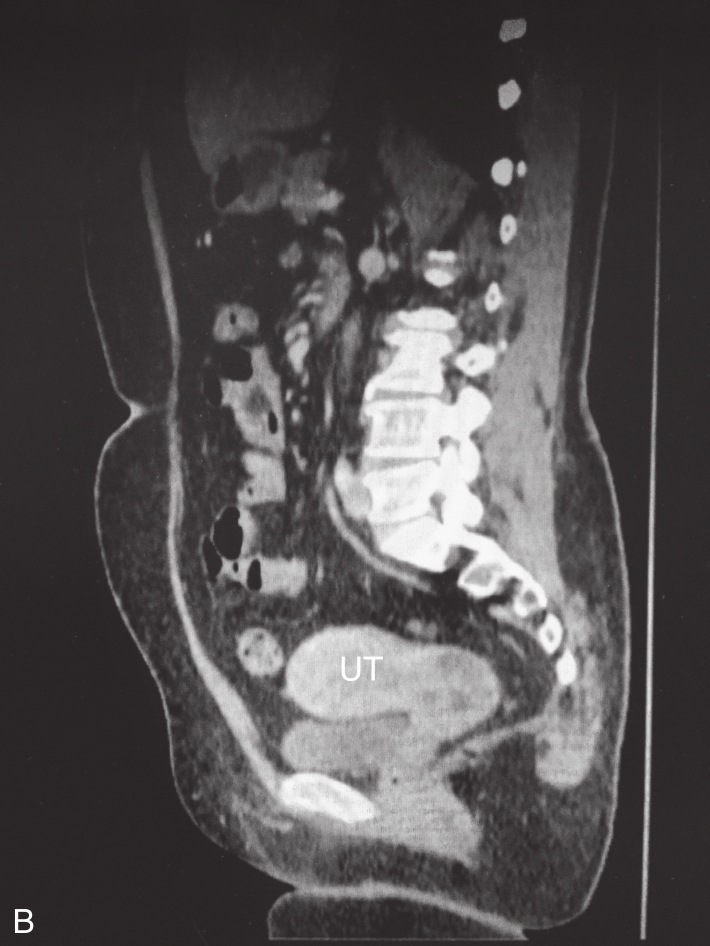

CT检查(入院当天)见图3-12-1,右侧闭孔区淋巴结稍增大,大血管旁未见增大淋巴结;右附件区稍增厚,可见小囊状影。

图3-12-1 盆腔CT图像

A.盆腔子宫底横切面;B.盆腹腔子宫矢状面。UT:子宫。